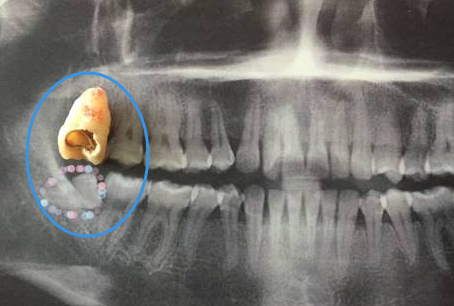

這樣的殘根是需要拔除的

一顆牙齒蛀牙嚴(yan) 重爛掉了,去拔牙要多少錢